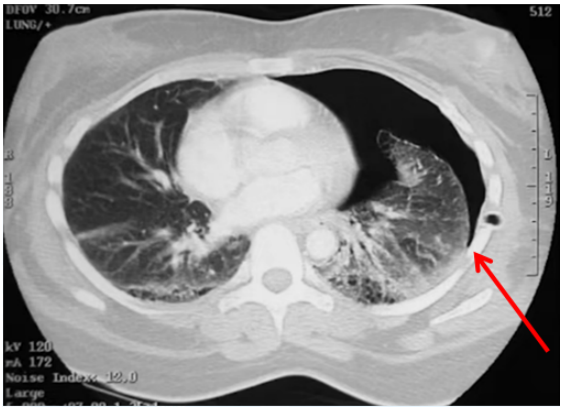

肺点是诊断气胸的金标准。CT图像箭头所指就是胸膜被分离之处(图10)。为什么会出现肺点?在超声图像中,我们可以看到,在分离点的下侧,也就是患者背侧,两个胸膜挨在一起,随着呼吸运动,胸膜有相对滑动,但在分离点以上,超声可以看到壁层胸膜,看不到脏层胸膜,因为它被气体挡住了,超声无法穿透气体,所以我们看到的是没有胸膜滑动的A线,这就是经典的肺点表现。

图片

图10  胸膜分离